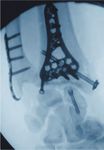

C1 Fraktur, Versorgung mit volarer Platte (breit)

Präoperativ

Postoperativ

Klinischer Fall und CT-Aufnahmen mit freundlicher Unterstützung der

Klinik und Poliklinik für Unfall-, Hand- und Wiederherstellungschirurgie

Universitätsklinikum Gießen und Marburg GmbH